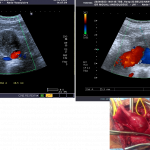

Le diagnostic des thromboses aortiques présente une complexité notable, nécessitant une approche méthodique et l’utilisation de technologies d’imagerie avancées. Les thromboses aortiques, qui consistent en la formation de caillots sanguins dans l’aorte, peuvent entraîner des complications graves si elles ne sont pas identifiées et traitées rapidement. Les techniques diagnostiques les plus couramment employées incluent l’écho-doppler artériel et le scanner thoraco-abdominal injecté, chacune offrant des avantages uniques pour la détection des anomalies vasculaires.

L’écho-doppler artériel est souvent la première étape dans l’évaluation des thromboses aortiques. Cette technique utilise des ultrasons pour visualiser le flux sanguin et détecter toute obstruction ou anomalie dans l’aorte. L’écho-doppler permet non seulement de confirmer la présence d’une thrombose mais aussi d’évaluer sa taille et son emplacement précis. Toutefois, cette méthode peut être limitée par la qualité de l’image obtenue, surtout chez les patients ayant une anatomie complexe ou de l’athérosclérose avancée.

En complément, le scanner thoraco-abdominal injecté, également appelé angioscanner, est une technique d’imagerie par tomodensitométrie (CT) qui fournit des images détaillées de l’aorte et de ses branches. En injectant un produit de contraste intraveineux, l’angioscanner permet de visualiser avec précision les structures vasculaires et d’identifier les thromboses aortiques de manière plus fiable. Cette procédure est particulièrement utile pour évaluer l’étendue des thromboses et planifier une intervention chirurgicale si nécessaire. Cependant, l’exposition aux radiations et les réactions possibles au produit de contraste sont des facteurs à considérer.